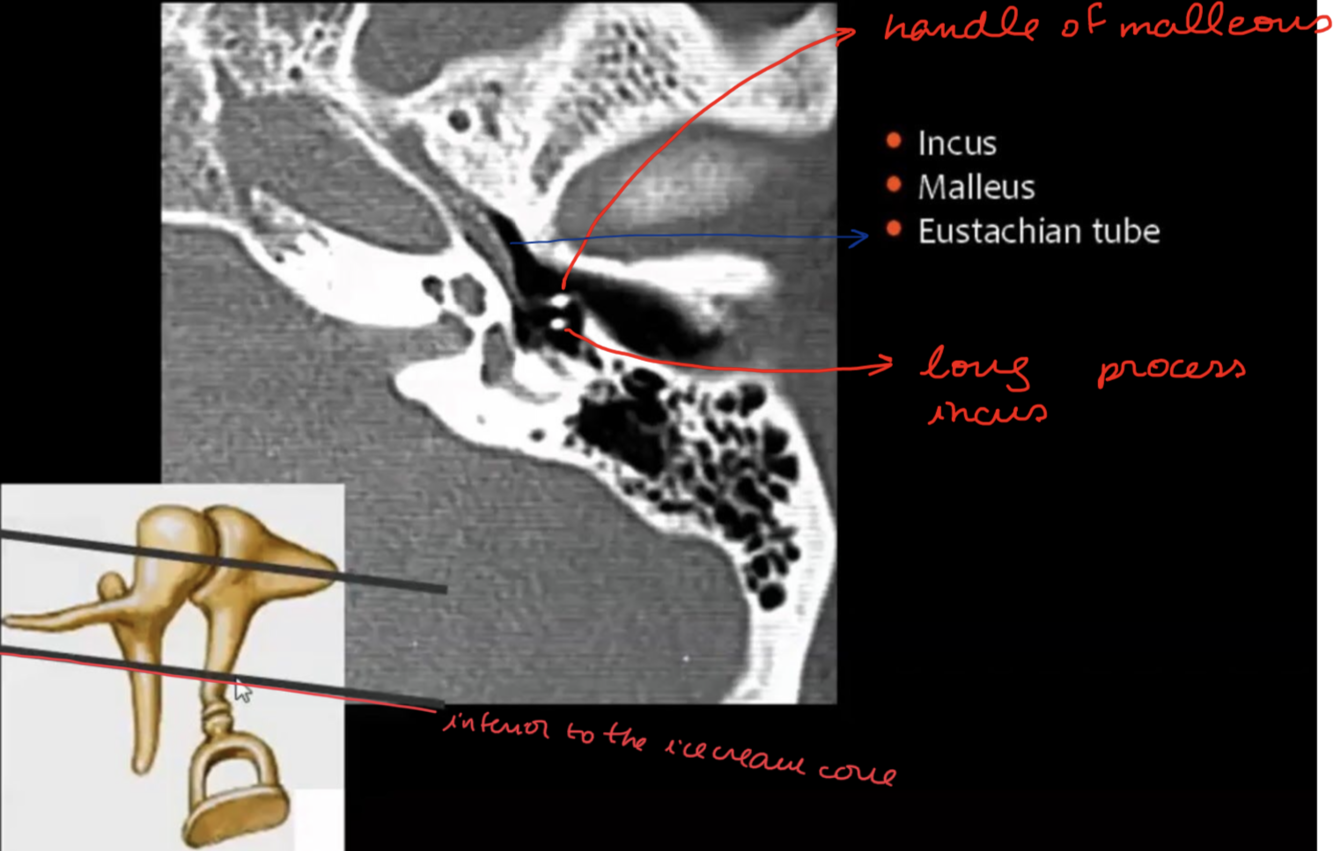

What are the ossicules of middle ear?

Description?